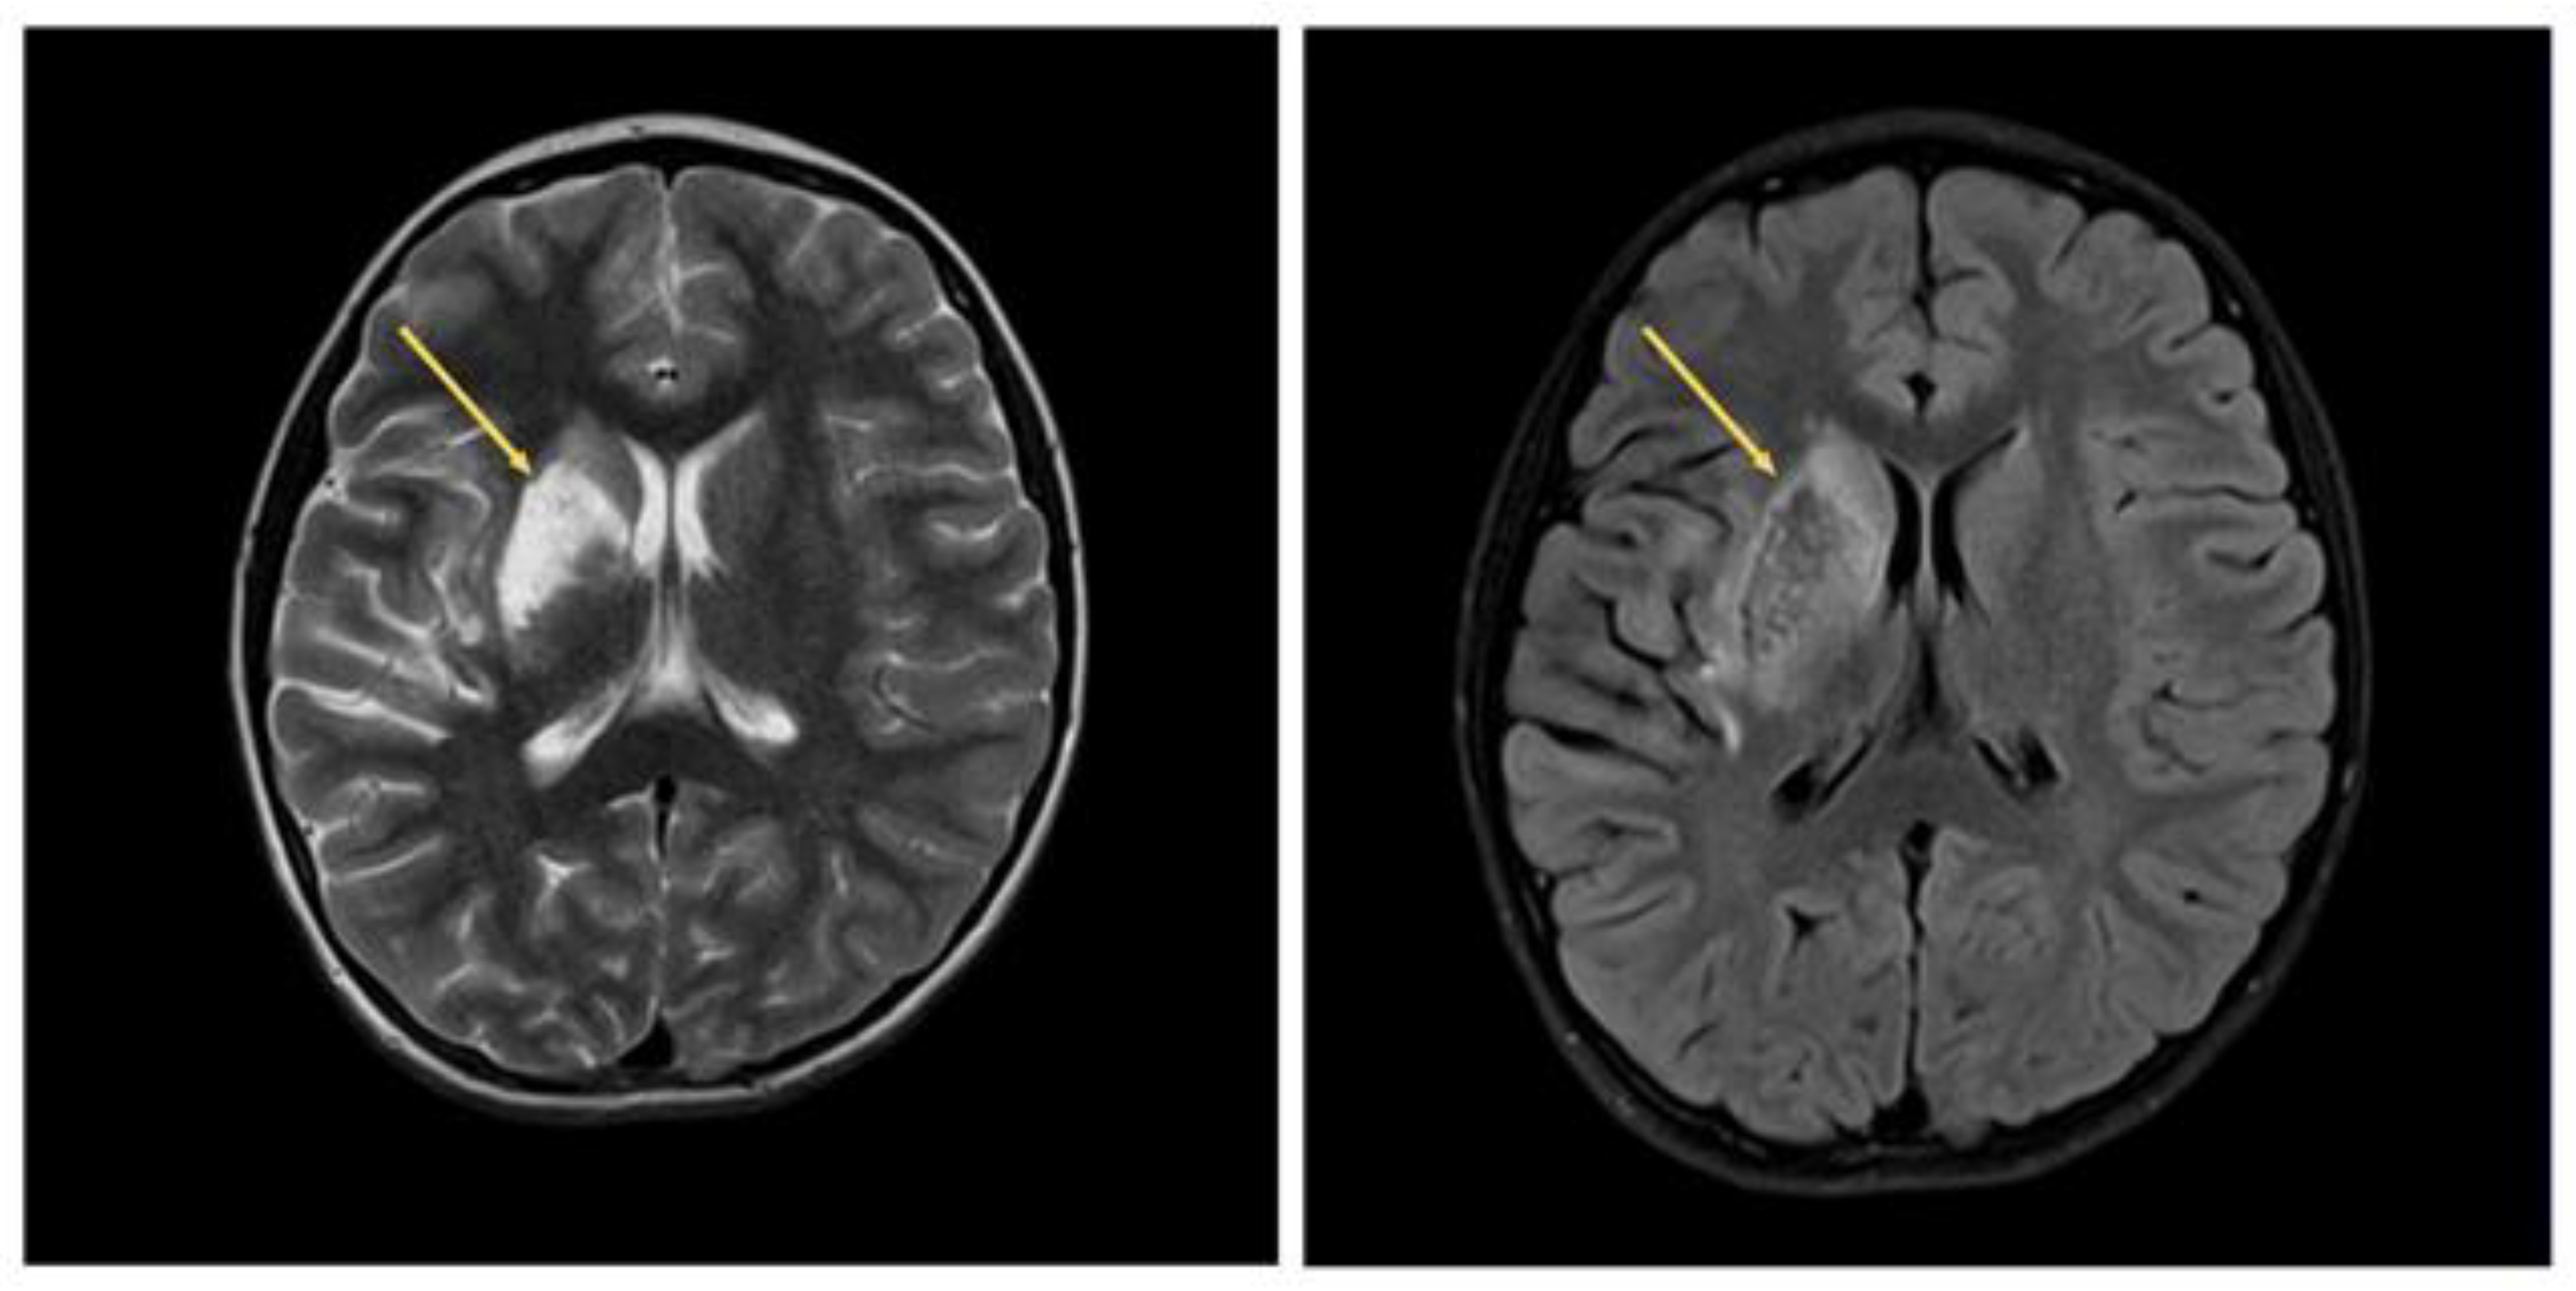

From the brain MRI, there was restoration of patency of the right MCA with an MR picture of postischemic cystic−gliotic changes in the territory of the right middle cerebral artery observed (Figure 7).

Figure 7.

Brain MRI. Arrows indicate postischemic cystic−glial changes in the territory of the right middle cerebral artery.